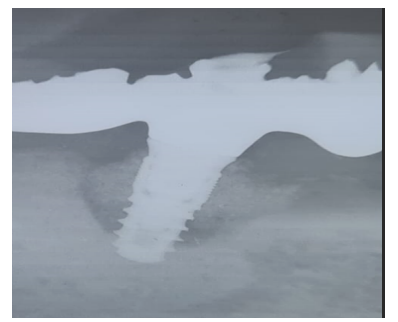

At 15 days post-surgery after suture removal (Figures 43) and at six months during the follow-up endoral X-ray (Figure 44).

Figure 43

Figure 44

Radiographically, we can observe an increase in bone level around the implant (Figure 46).

Figure 46